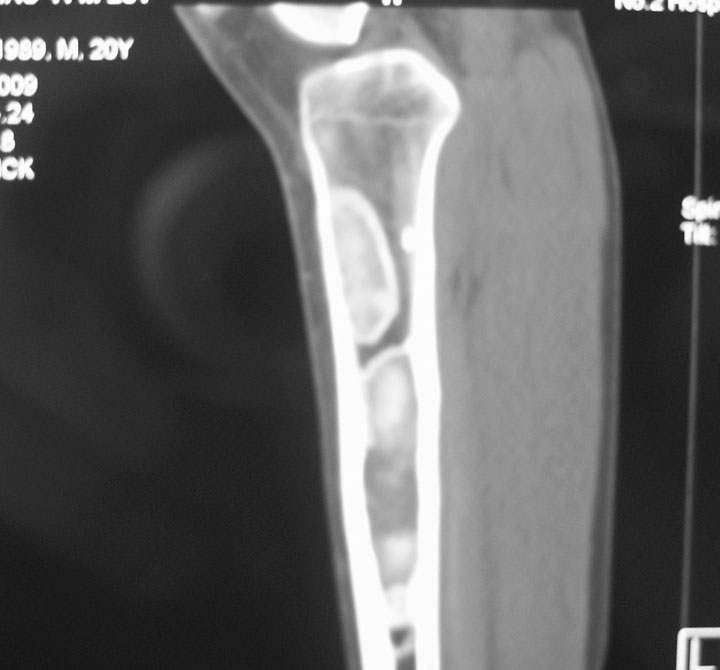

标题: CT19885:左胫骨上端肿瘤。 [打印本页]

标题: CT19885:左胫骨上端肿瘤。

男,20岁,医学院学生,11年前感左胫骨上端劳累后酸痛,曾由父母带到国内好几家有名望的医院诊治,但众说不一,所以基本上没有治疗。今年三月又开始出现症状,又到多家省级医院求治,但专家们的意见还是不能统一。各生化检查正常。mri考虑到胫骨上端良性血管瘤可能性大。ct考虑纤维瘤可能性大。请各位发表高见。

考虑胫骨多发性内生骨瘤。

胫骨多发性内生骨瘤可能。

考虑左胫骨良性骨肿瘤或骨肿瘤样病变(多发性内生骨瘤?骨纤维结构不良?)。

考虑胫骨多发性内生骨瘤可能。应该传骨窗。

考虑左胫骨良性骨肿瘤或骨肿瘤样病变(多发性内生骨瘤?骨纤维结构不良?)。骨梗死,纤维瘤。